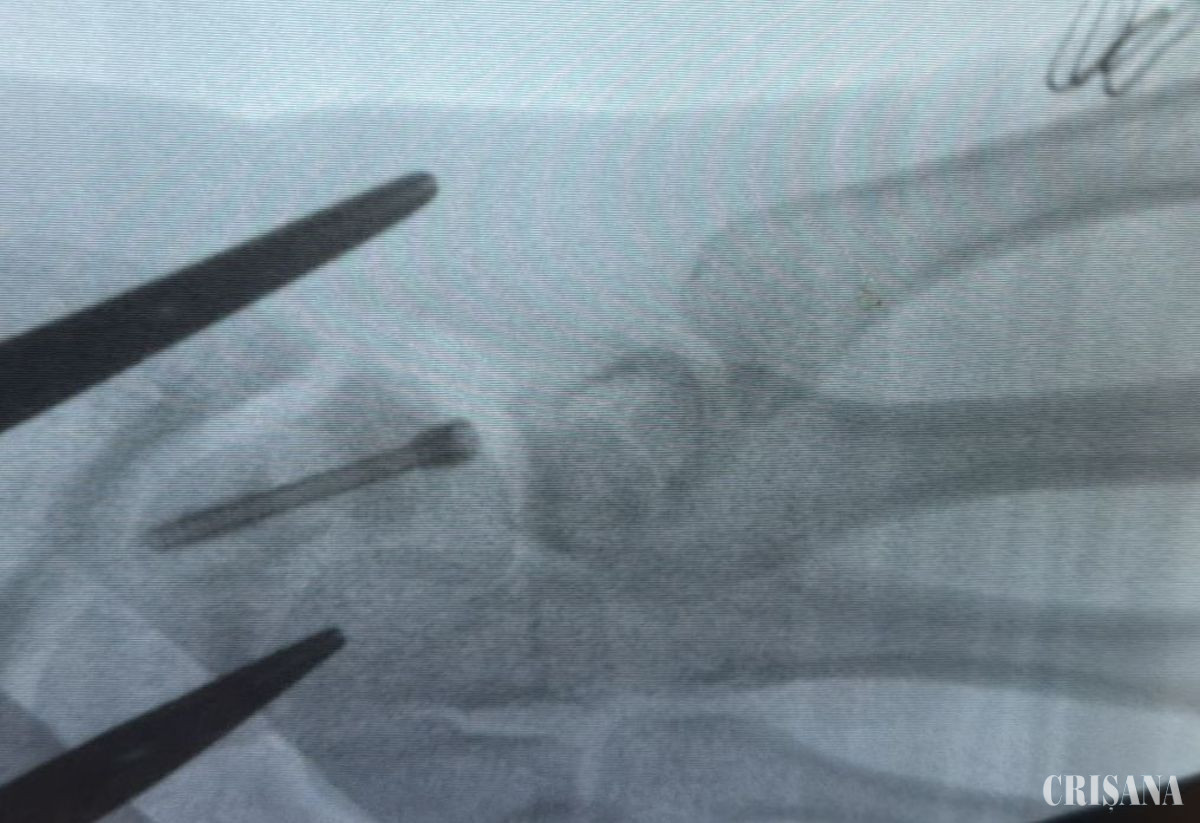

La aproape un an de la traumatism, persistența durerii și limitarea funcției mâinii au impus trimiterea pacientului dintr-o altă unitate spitalicească pentru tratament chirurgical de specialitate. Potrivit unui comunicat transmis de Spitalul Clinic Județean de Urgență Bihor, la 11 luni de la accident, pacientul prezenta dureri importante la nivelul articulației radio-carpiene, cu limitarea severă a mișcărilor, scăderea forței mâinii drepte și imposibilitatea de a-și îndoi încheietura. În urma investigațiilor imagistice (RMN, radiografii) și a consulturilor de specialitate, medicul curant, Dr. Alexandru Pîrvan a diagnosticat pacientul cu fractură de os scafoid drept, cu deficit de consolidare, evoluată către pseudoartroză, asociată cu ruptură parțială a ligamentului scafo-lunar. Fractura de scafoid afectează un os mic, dar extrem de important al încheieturii mâinii, care face legătura între oasele antebrațului și cele ale mâinii și contribuie decisiv la stabilitatea și mobilitatea acestei articulații. Deși mic ca dimensiune, scafoidul are un rol esențial în funcția mâinii. Acest tip de fractură apare, de regulă, în urma unei căderi pe mâna întinsă sau a unui traumatism sportiv. Fractura de os scafoid cu acest tip de evoluție se remarcă prin raritatea și complexitatea sa. În general, durerea inițială este redusă, motiv pentru care leziunea poate fi confundată cu o simplă entorsă. În plus, fractura nu este întotdeauna vizibilă pe radiografia efectuată imediat după traumatism, ceea ce poate întârzia stabilirea diagnosticului corect. Un aspect esențial îl reprezintă vascularizația limitată a osului scafoid, care face ca procesul de vindecare să fie lent și dificil. În absența unui tratament adecvat, fragmentele osoase pot să nu se mai consolideze, ducând la pseudoartroză, dureri persistente și, în timp, la artroză a încheieturii mâinii. Din aceste motive, deși inițial poate părea o leziune minoră, fractura de scafoid este o afecțiune care necesită atenție și tratament de specialitate, pentru a preveni consecințe severe asupra funcției mâinii. Această patologie este foarte rară, mai ales la pacienți tineri, iar stadiul avansat de pseudoartroză reprezintă un element de complexitate și raritate deosebită, fragmentele osoase neconsolidate formând o articulație falsă. Pacientul a fost programat pentru intervenție chirurgicală, care a avut loc în ultimele zile ale anului 2025. Operația a constat într-o incizie de aproximativ 5 cm, cu curățarea focarului de pseudoartroză la nivelul osului scafoid și stabilizarea fracturii prin montarea unui șurub Herbert, utilizând o tehnică chirurgicală specială. Acest tip de șurub se remarcă prin faptul că nu necesită extragere ulterioară, fiind conceput fără vârf, el rămâne în corp și după ce osul s-a vindecat. Durata intervenției a fost de aproximativ 2 ore și jumătate, iar evoluția post-operatorie a pacientului a fost favorabilă. Adolescentul a fost diagnosticat și operat în cadrul Secției Clinice Chirurgie și Ortopedie Pediatrică, de către Dr. Alexandru Pîrvan - medic specialist ortopedie pediatrică, pregătit la Centre Hospitalier de Luxembourg (CHL) și București. Din echipa operatorie au mai făcut parte dr. Samuel Piu - medic rezident ortopedie pediatrică și dr. Adriana Dobrescu, medic primar ATI, Secția Clinică ATI II. În ultimii ani, Spitalul Clinic Județean de Urgență Bihor a devenit un centru regional de referință pentru tratamentul cazurilor ortopedice pediatrice complexe, adresabilitatea crescând constant din județe precum Arad, Sălaj, Satu Mare, Maramureș, Hunedoara și Bistrița-Năsăud. Doar în anul 2025, echipa de ortopedie pediatrică a realizat peste 400 de intervenții chirurgicale, confirmând experiența și competența regională în managementul patologiilor osteo-articulare complexe. În Secția Clinică de Chirurgie și Ortopedie Pediatrică se efectuează în mod curent intervenții reconstructive osteo-articulare la nivelul șoldului, genunchiului și piciorului, pentru afecțiuni precum picior varus equin, picior plat valg, epifizioliză de șold, inegalități de membre pelvine sau genu valgum.